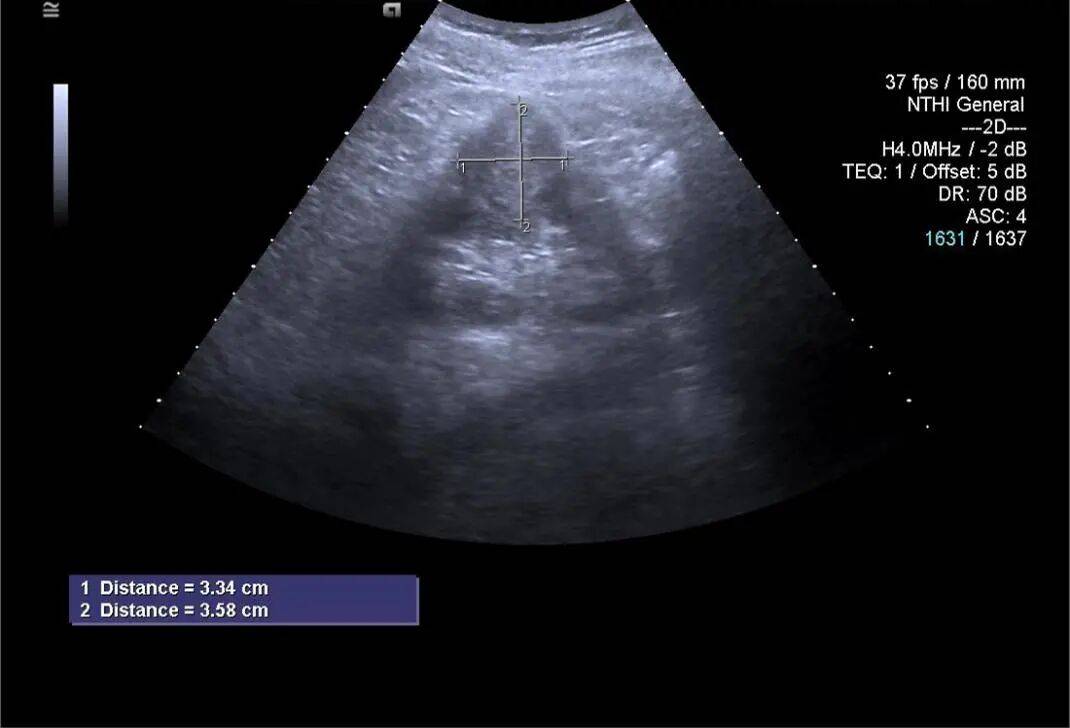

2. 左肾静脉增宽,前后径约 16 mm,其内充满低回声,下腔静脉增宽,前后径约 29 mm,其内充满低回声,向上延伸至右心房入口处。CDFI:左肾静脉、下腔静脉及其内低回声见星点状血流信号(图 3、4)。

图 3 灰阶超声示肾静脉及下腔静脉癌栓超声表现( RK 右肾 IVC 下腔静脉 L RV 左肾静脉 AAO 腹主动脉)